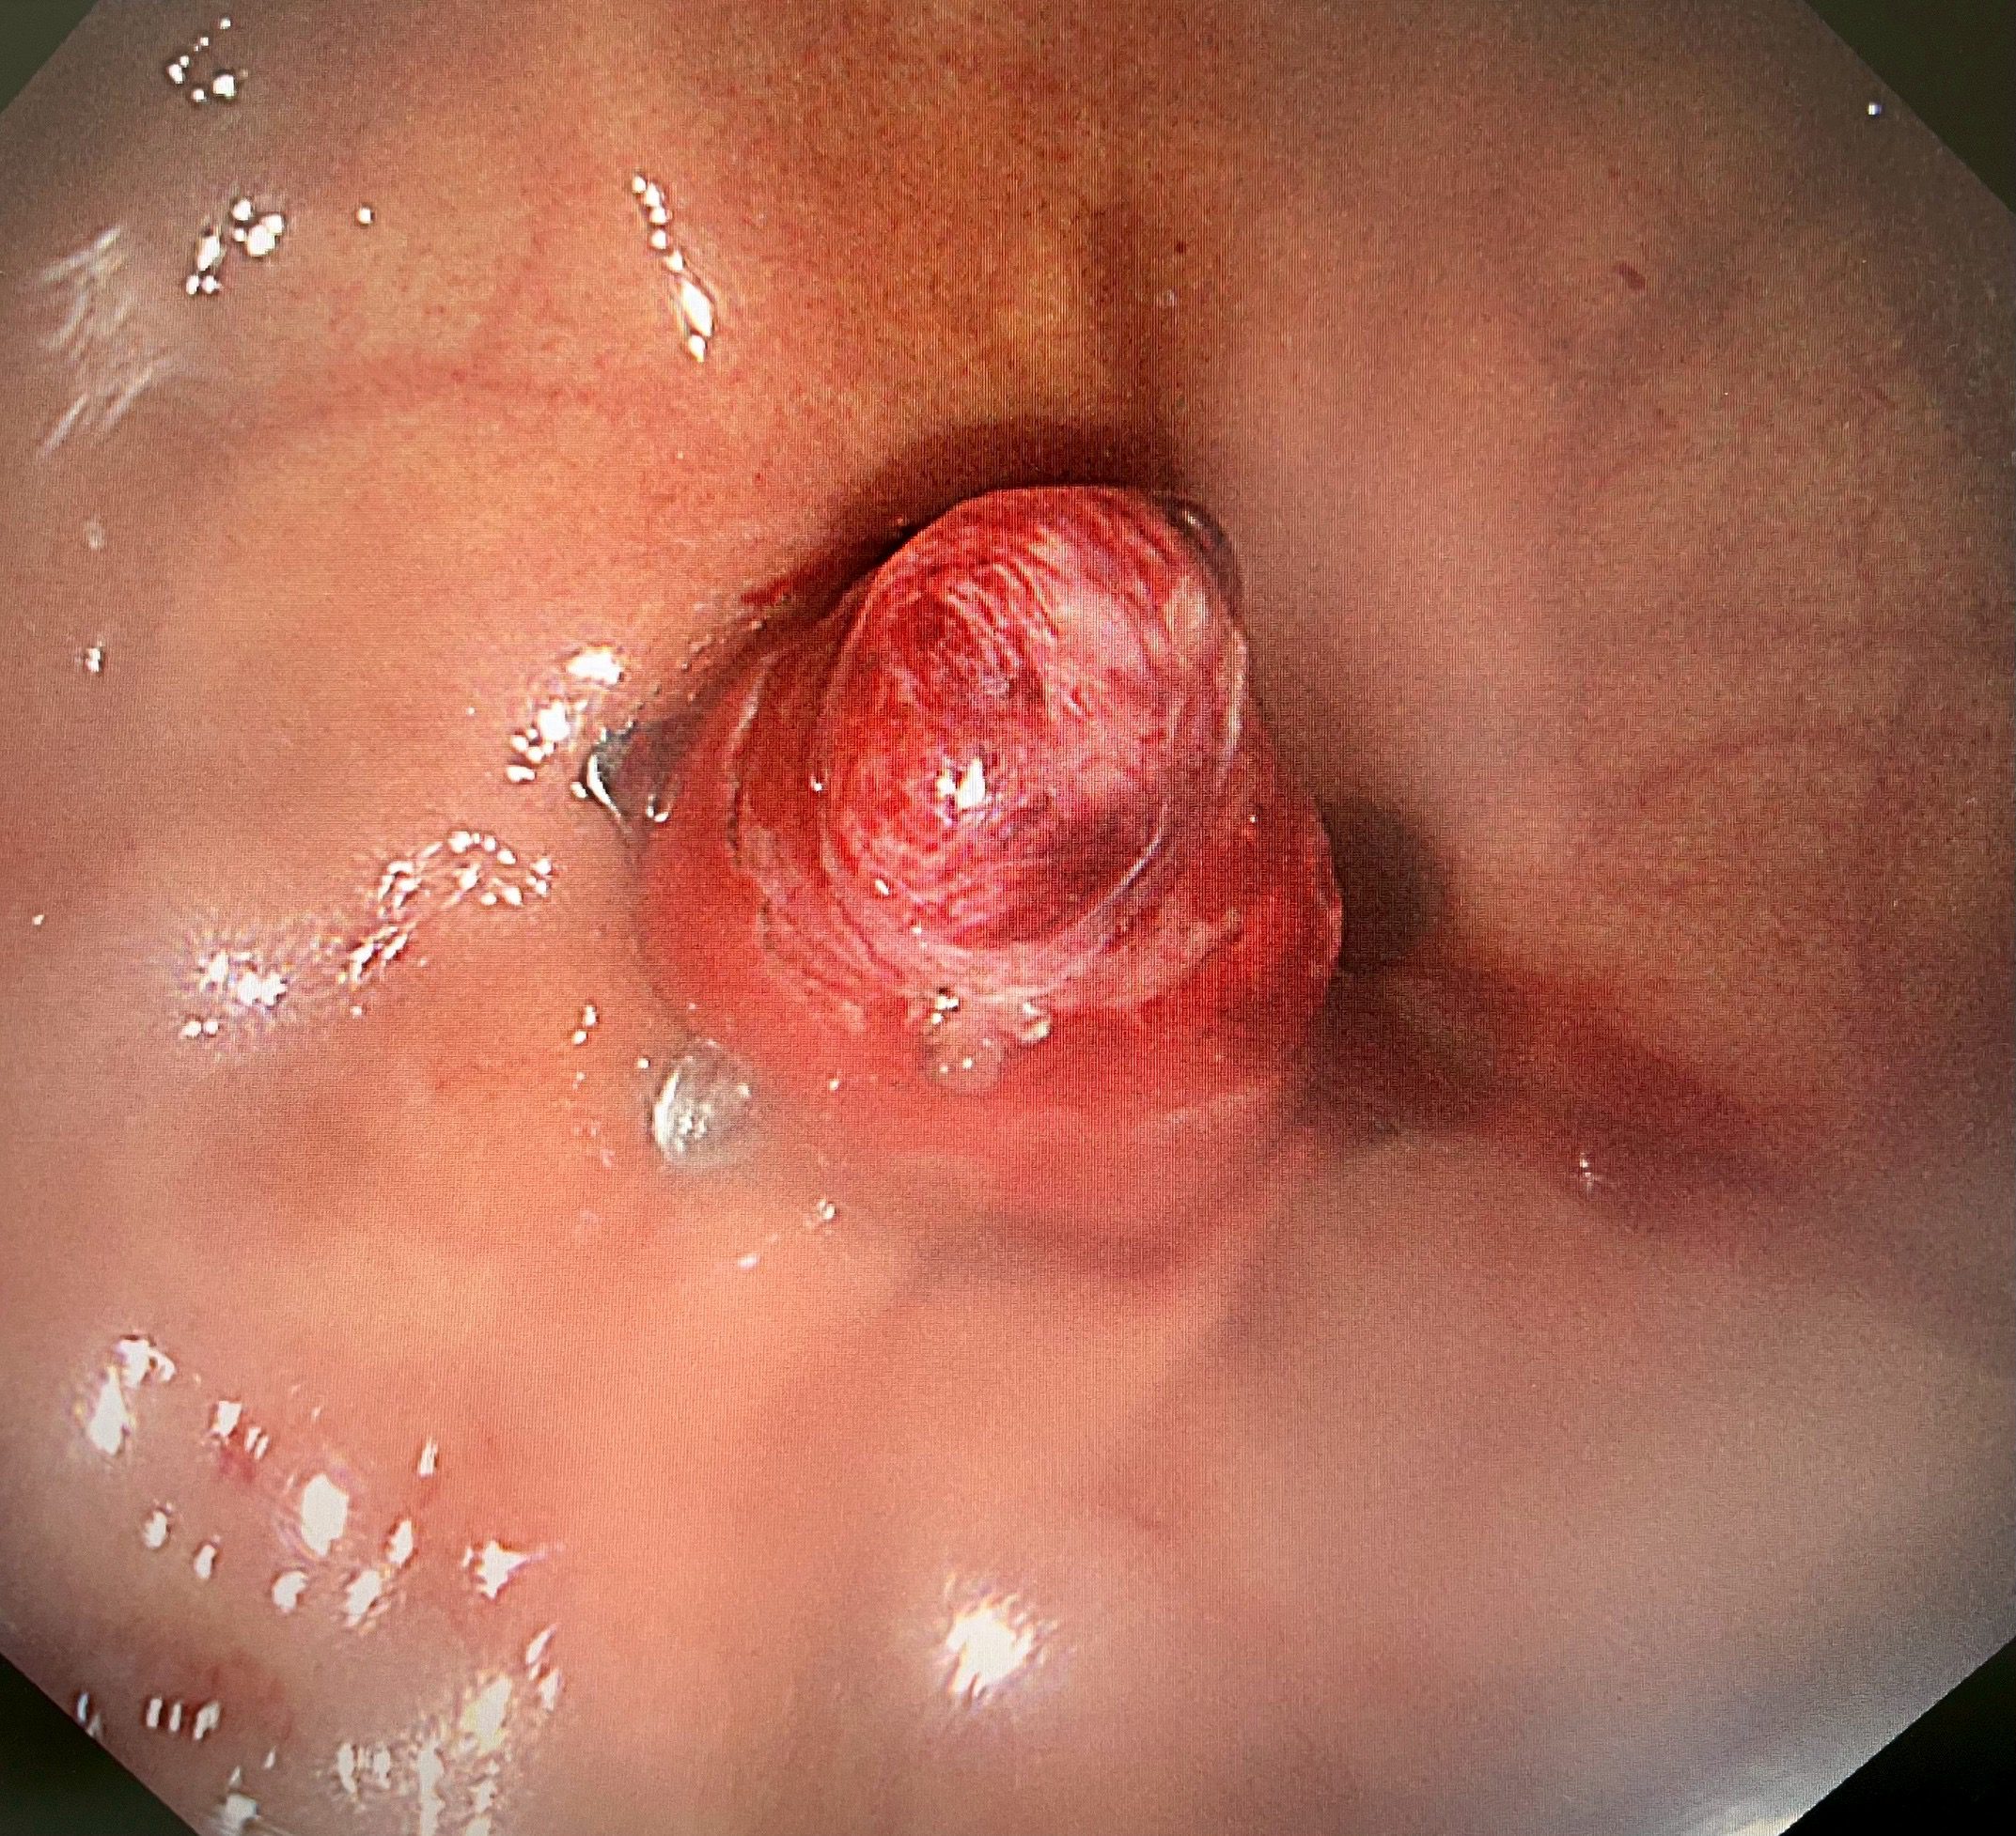

微創手術新突破:25分鐘完成全層切除(Endoscopic Full Thickeness Resection,EFTR)

傳統上,這類腫瘤需要透過腹腔鏡或開腹手術切除,甚至需要切除部分胃壁,患者術後往往需要住院多日,恢復時間較長。然而,隨著內視鏡技術的進步,現在已有更微創的選擇。

陳鴻運醫師採用新式的「內視鏡全層切除術」(EFTR)配合「pad lock clip closure device」閉合器械,僅花了25分鐘就成功將腫瘤完整切除(En Bloc resection)。這種技術能夠完整切除胃壁全層的病變,同時使用特殊夾具迅速閉合創口,避免胃內容物外漏導致腹膜炎等併發症。

「手術過程非常順利」,陳鴻運醫師描述:「我們透過內視鏡直視下將腫瘤完整切除,並立即使用pad lock clip閉合裝置關閉胃壁缺損。患者麻醉醒後完全沒有任何不適,沒有腹痛、腹脹等症狀。」